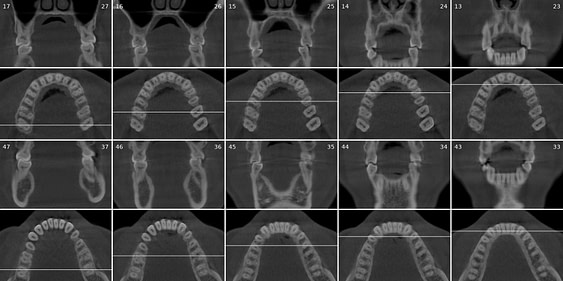

Diagnocat generates OPG and frontal and lateral cephalometric reconstructions from the CBCT data.

Tracings of the maxilla, mandible, central incisors, canines and molars. All automatically.

Cross-sectional and coronal views of teeth show torque and buccolingual relationships such as crossbite.

TMJ coronal/sagittal slices and summations visualize abnormal positioning/shape of the mandibular condyle.

The orthodontic report generates OPG and front/lateral cephalograms. These are not as sharp as true OPG and cephalograms. Tracings of the maxilla, mandible, central incisors, canines, and molars are automatically produced on the generated frontal/lateral cephalogram.

I showed the orthodontic report to an orthodontist colleague. She found the tracings to be fairly accurate compared to a real lateral cephalogram of the same patient. She did further tracings on the generated lateral ceph and advised it was difficult to visualize points such as Nasion, ANS, A Point, Condylion, and Orbitae and visualize the fourth vertebrae to determine peak growth phase. Furthermore, other orthodontic software can automatically calculate skeletal/dental relationships, planes, and angles.